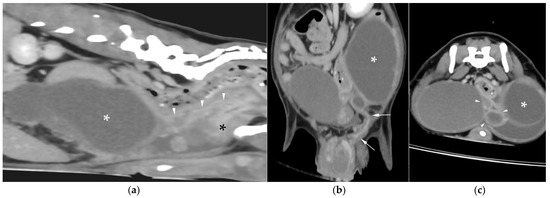

Uterus masculinus is a rare disorder of sexual development in males, characterized by the presence of tubular female genitalia. Diagnostic imaging reports of infected uterus masculinus are limited. We describe the ultrasonographic and computed tomographic findings in three dogs, all presenting with abdominal distension, pain, and systemic infection. Imaging consistently revealed a fluid-filled, bicornuate structure arising from the prostate. In two dogs, the horns extended through the inguinal rings to the scrotal testes; in the third, with a prior left orchiectomy, both horns were intra-abdominal, the right ending in a peritoneal mass. Surgery and histopathology confirmed infected uterus masculinus, with Escherichia coli isolated from urine in all dogs and from the structure in two. Two dogs had Leydig cell tumors, one with concurrent uterine neoplasia; the third had an ovarian or ovotesticular granulosa cell tumor. Although rare, infected uterus masculinus is potentially life-threatening and should be considered in male dogs with abdominal pain, distension, or systemic infection. This is the first case series describing combined ultrasonographic and tomographic features of infected uterus masculinus, including novel findings such as cervix-like mural narrowing and fluid–fluid levels. It is also the first imaging description of an ovarian or ovotesticular tumor in a dog with uterus masculinus. Full article

Figure 1